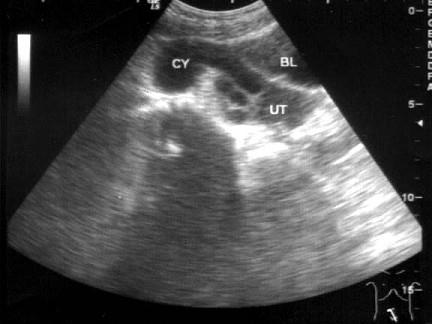

问题 患者女27岁,下腹部疼痛数月,体检:右侧附件区增厚、增大,B超检查如图所示应诊断为 ( )

选项 A、盆腔积液 B、卵巢癌 C、右侧输尿管扩张 D、右侧输卵管积液 E、右侧卵巢囊肿

答案 D